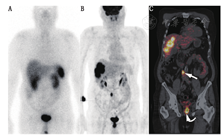

GEP NETs患者的管理取决于肿瘤的分级和SSTR表达。分子成像有助于检测肿瘤的异质性,并指导临床医师寻求最佳的治疗方案。此外,肿瘤分级和放射性标记的SSAs(或18F-FDOPA)及18F-FDG PET/CT功能显像结果之间存在潜在的翻转现象。放射性标记的SSAs(或18F-FDOPA)高摄取和18F-FDG低摄取的不匹配被广泛认为是低级别GEP NETs功能显像表现形式;相反,放射性标记的SSAs(或18F-FDOPA)低摄取和18F-FDG高摄取则提示高级别肿瘤(图7)。